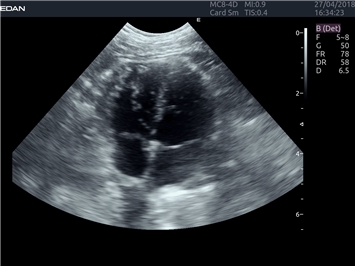

EDAN Acclarix LX4 VET представляет собой профессиональную ультразвуковую систему, специально разработанную для ветеринарных исследований. Сочетание стабильности, высокой производительности и эффективности делает эту систему идеальным выбором для современной ветеринарной практики.

Тканевой допплер:

Да

Анатомический М-режим:

Цветной M-режим:

M-режим: